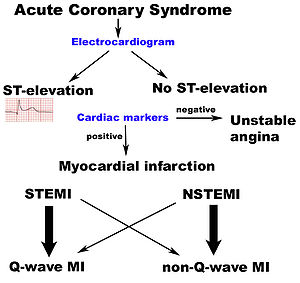

The patient will receive a number of diagnostic tests, such as an electrocardiogram (ECG, EKG), a chest X-ray and blood tests to detect elevations in cardiac markers (blood tests to detect heart muscle damage). The most often used markers are the creatine kinase-MB (CK-MB) fraction and the troponin I (TnI) or troponin T (TnT) levels. On the basis of the ECG, a distinction is made between ST elevation MI (STEMI) or non-ST elevation MI (NSTEMI). Most cases of STEMI are treated with thrombolysis or if possible with percutaneous coronary intervention (PCI, angioplasty and stent insertion), provided the hospital has facilities for coronary angiography. NSTEMI is managed with medication, although PCI is often performed during hospital admission. In patients who have multiple blockages and who are relatively stable, or in a few extraordinary emergency cases, bypass surgery of the blocked coronary artery is an option.

Acute myocardial infarction is a type of acute coronary syndrome, which is most frequently (but not always) a manifestation of coronary artery disease. The acute coronary syndromes include ST segment elevation myocardial infarction (STEMI), non-ST segment elevation myocardial infarction (NSTEMI), and unstable angina (UA).

The diagnosis of myocardial infarction is made by integrating the history of the presenting illness and physical examination with electrocardiogram findings and cardiac markers ( blood tests for heart muscle cell damage). A coronary angiogram allows visualization of narrowings or obstructions on the heart vessels, and therapeutic measures can follow immediately. At autopsy, a pathologist can diagnose a myocardial infarction based on anatomopathological findings.

The 12 lead ECG is used to classify patients into one of three groups:

- those with ST segment elevation or new bundle branch block (suspicious for acute injury and a possible candidate for acute reperfusion therapy with thrombolytics or primary PCI),

- those with ST segment depression or T wave inversion (suspicious for ischemia), and

- those with a so-called non-diagnostic or normal ECG.